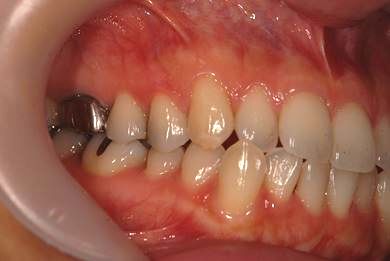

| 性別/年齢 | 女性 / 34歳 | ||||||||||||||||||||||||||||||||

| 主訴 | 以前虫歯を治療して金属を入れたところが、再び虫歯になったのか、軽くしみたり違和感がある。 | ||||||||||||||||||||||||||||||||

| 治療方針 | セラミック治療にて、審美的回復を行う。 | ||||||||||||||||||||||||||||||||

| 治療内容 | メタルボンドセラミッククラウン1本(メタルボンド用土台1本) | ||||||||||||||||||||||||||||||||

| 総治療費 | 125,685円 | ||||||||||||||||||||||||||||||||

| 治療期間 | 3ヶ月 |